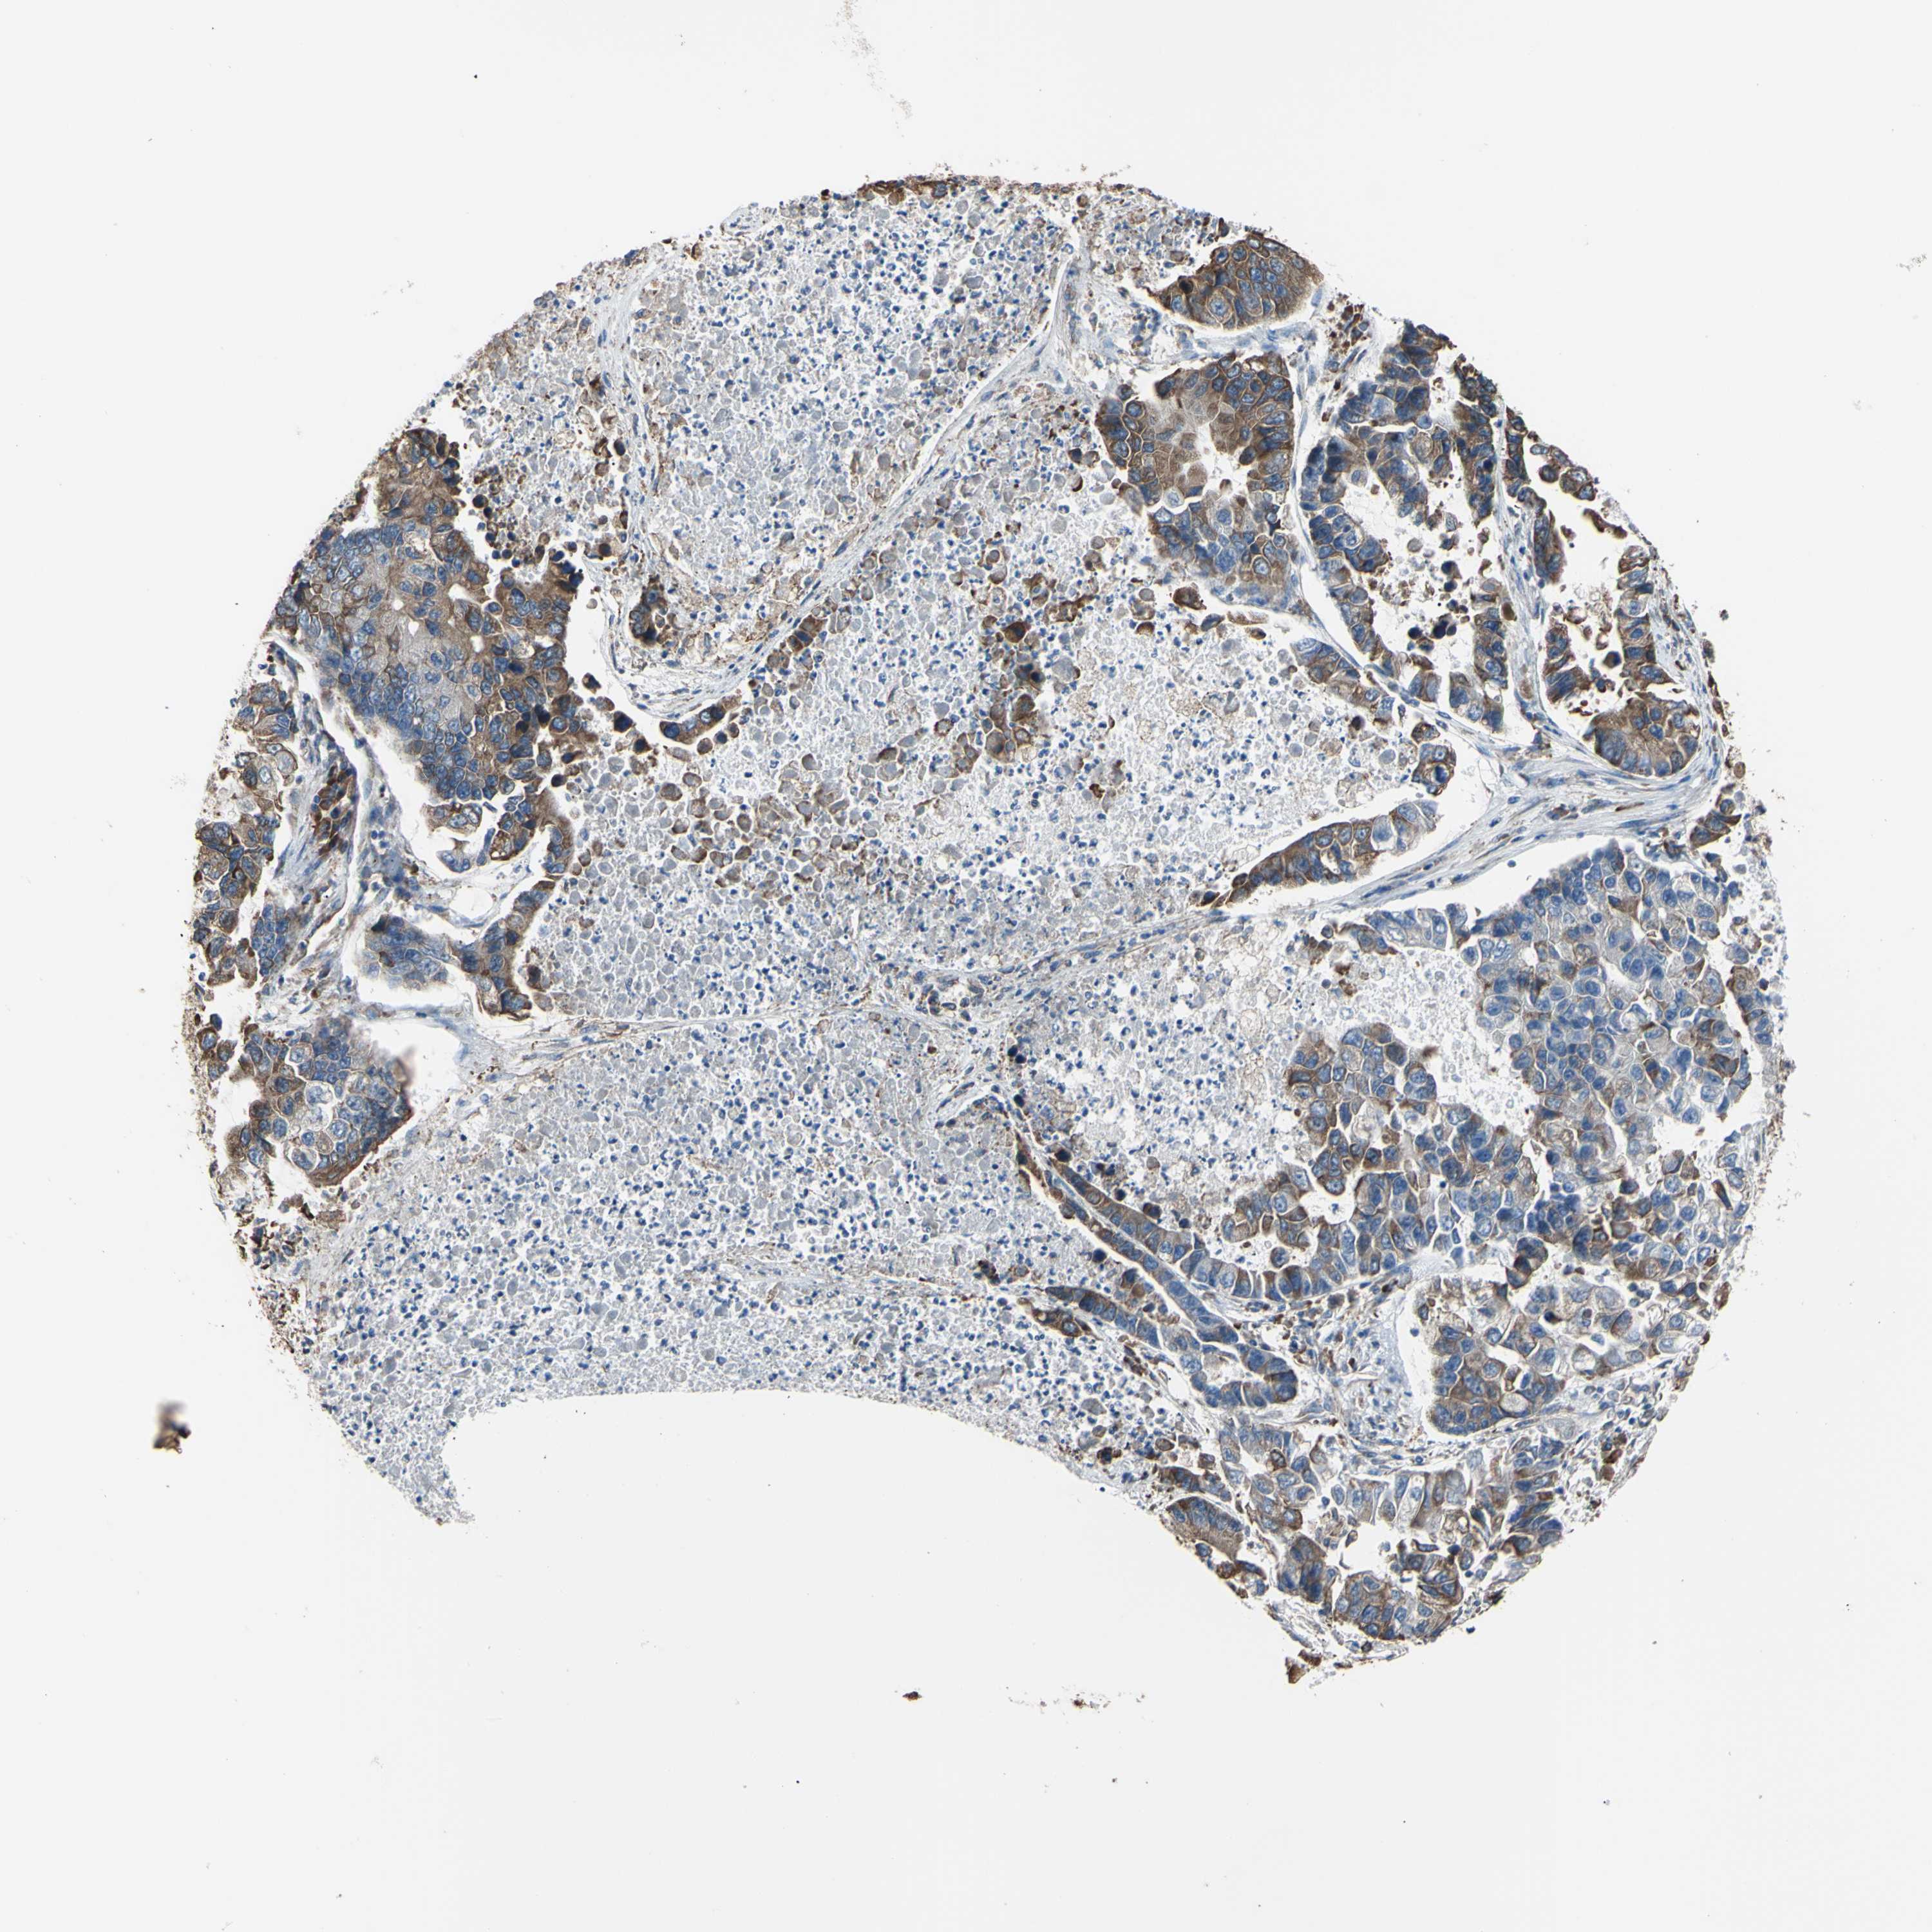

CANCER LUNG CANCER Show tissue menu

LUAD TCGA LUAD VALIDATION LUSC TCGA LUSC VALIDATION PROTEIN LUAD CPTAC PROTEIN LUSC CPTAC PROTEIN EXPRESSION